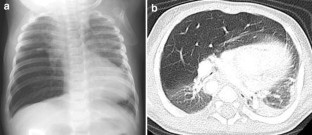

Fig. 2